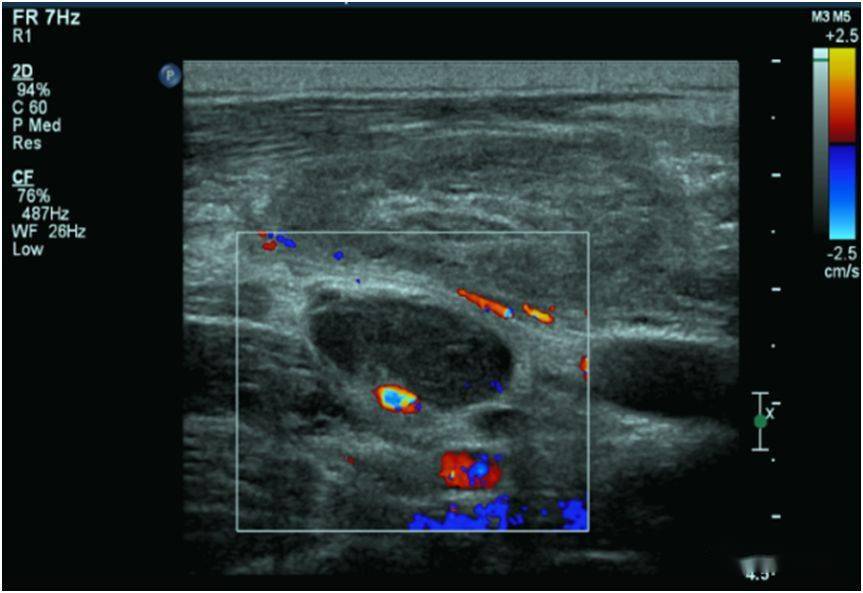

超声主任从彩超上看这个淋巴结的很多征象都提示它是恶性的,鼻咽癌

淋巴结血流信号超声特点